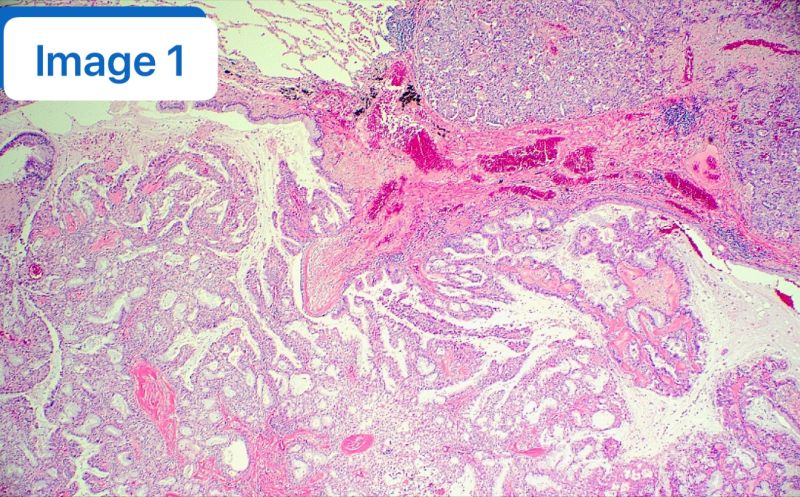

分享一个极具欺骗性的肺部病理诊断陷阱:纤毛黏液结节性乳头状肿瘤(CMPT)。这是一种罕见的良性病变,但在小标本活检中,它极具“伪装性”,极易被误诊为浸润性黏液腺癌。 📝 【病例回顾】 🔪 【反转与真相】 患者随后接受了手术切除,但大体标本的切片却讲述了一个完全不同的故事。 显微镜下呈现出了 CMPT 的经典特征(见附图): 🔬 【免疫组化(IHC)一锤定音】 ⚠️ 【诊断陷阱在哪里?】 为什么穿刺活检会误诊? 因为在局限的穿刺小标本中,往往只能看到大量的黏液和腺体结构,而具有鉴别意义的纤毛和基底细胞可能刚好缺失,或者在穿刺过程中被挤压破坏。病理医生一旦只看到“黏液+腺体”,很容易条件反射地诊断为黏液性腺癌。 💡 【Clinical Pearls / 临床启示】 这个病例完美诠释了形态学、免疫表型和临床背景结合的重要性。它警示我们:在有限的活检标本上,面对富含黏液的病变时,下“癌”的诊断一定要慎之又慎!